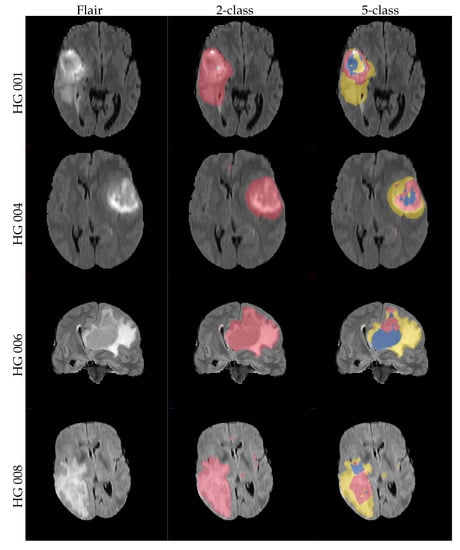

Figure 2.

Four example slices from volumes of the in-house dataset that contain sparse and positive annotations. Most other slices of the volumes are annotation-free; at most one or two contain smaller additional annotations. The non-affected tissue is not annotated.